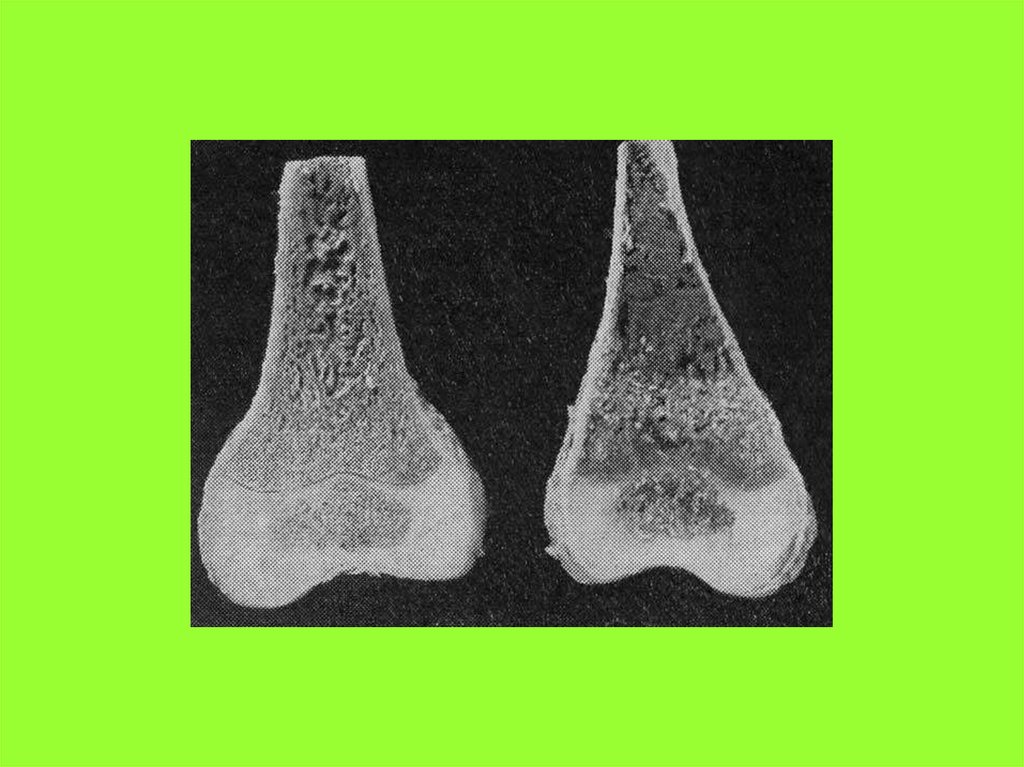

Физиология обмена витамина Д,

минералов кальция и фосфора

В минерализации костей участвуют

несколько органов и систем.

К ним относятся:

•Кожа и подкожно-жировая клетчатка

•Желудочно-кишечный тракт (ЖКТ)

•Почки

•Щитовидная и паращитовидная железы